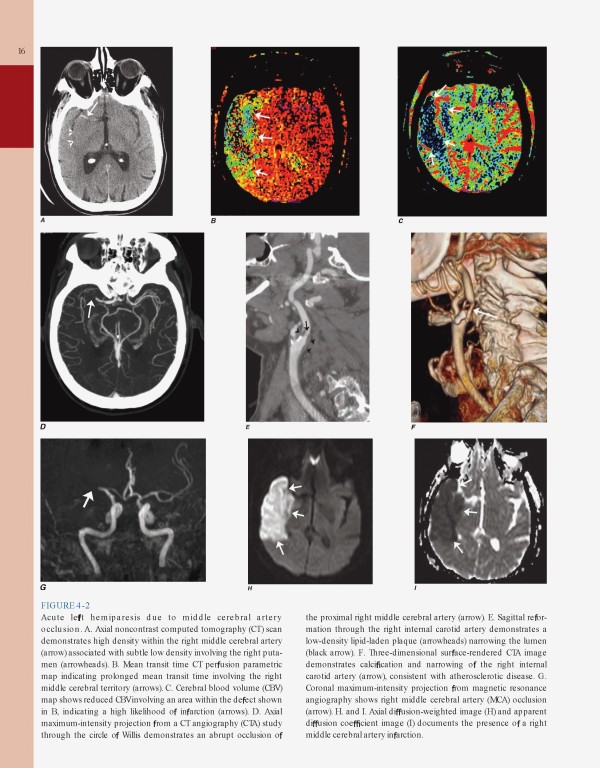

کتاب Harrisons Neurology in Clinical Medicine 4th edition | مغز و اعصاب در پزشکی بالینی هاریسون 2018 یک همراه بالینی مختصر و تمام رنگی که دارای مجموعه‌ای عالی از فصول مرتبط با نورولوژی برگرفته از اصول طب داخلی هریسون، نسخه نوزدهم می‌باشد.

• Current, complete coverage of clinically important topics in neurology, including Clinical Manifestations of Neurologic Diseases, Diseases of the Nervous System, Chronic Fatigue Syndrome, Psychiatric Disorders, and Alcoholism and Drug Dependency

• Extensively updated to highlight recent advances in the understanding, diagnosis, treatment, and prevention of neurologic and psychiatric disorders; expanded coverage of neurodegenerative diseases; extensively revised chapter on cerebrovascular diseases; the latest breakthroughs in sleep disorders and migraine

• Enhanced by numerous neuroimaging figures throughout the text and an expanded atlas of neuroimaging findings